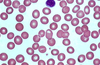

How do you describe this smear?

Normocytic, normochromatic, 1/3 central palor.